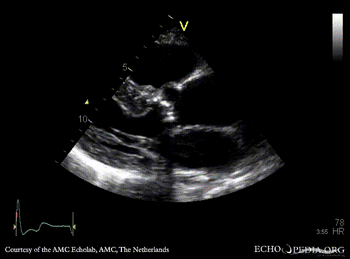

Severe aortic valve stenosis and plaque in abdominal aorta

PSAX: stenosis of aortic valve PLAX with Color Doppler: high velocity transaortic flow, mild aortic regurgitation